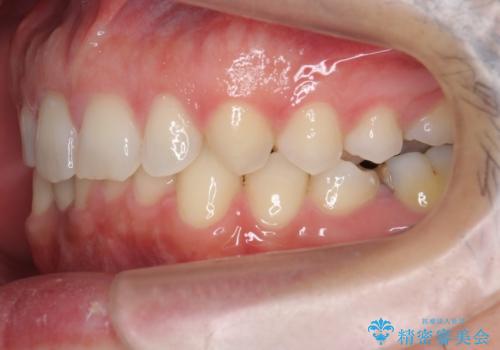

歯の位置が悪く、隙間も大きいためセラミックで被せても到底思ったような仕上がりにならないこと、下の歯が咬み込んでいるためセラミックはおろか前歯が短期間で折れてしまうリスクが非常に高いことを説明しました。

上はインビザラインで目立たないように前歯を下げ、下は難しいため、ワイヤー矯正で咬み込んでいる下の歯を沈める処置を初め行いました。最終的には上下ともインビザライン矯正で仕上げました。

下の前歯が生まれつき1本少なかったため、その部分には最終的にインプラントを入れ、下の歯が下がりすぎないようにかつ上の前歯にしっかり咬むように仕上げました。

すきっ歯を被せものだけで治そうとすると、横幅の広い巨大な歯になり、理想的な仕上がりとは程遠いです。

また、歯の位置が悪いままかぶせると、無理な角度補正をすることになり、歯も割れやすいです。

今回は、時間はかかりましたが矯正治療で隙間を閉じ、天然の歯を保存することができました。セラミックで無理に一時的にかぶせるとその後大変な人生になるのが予想されます。